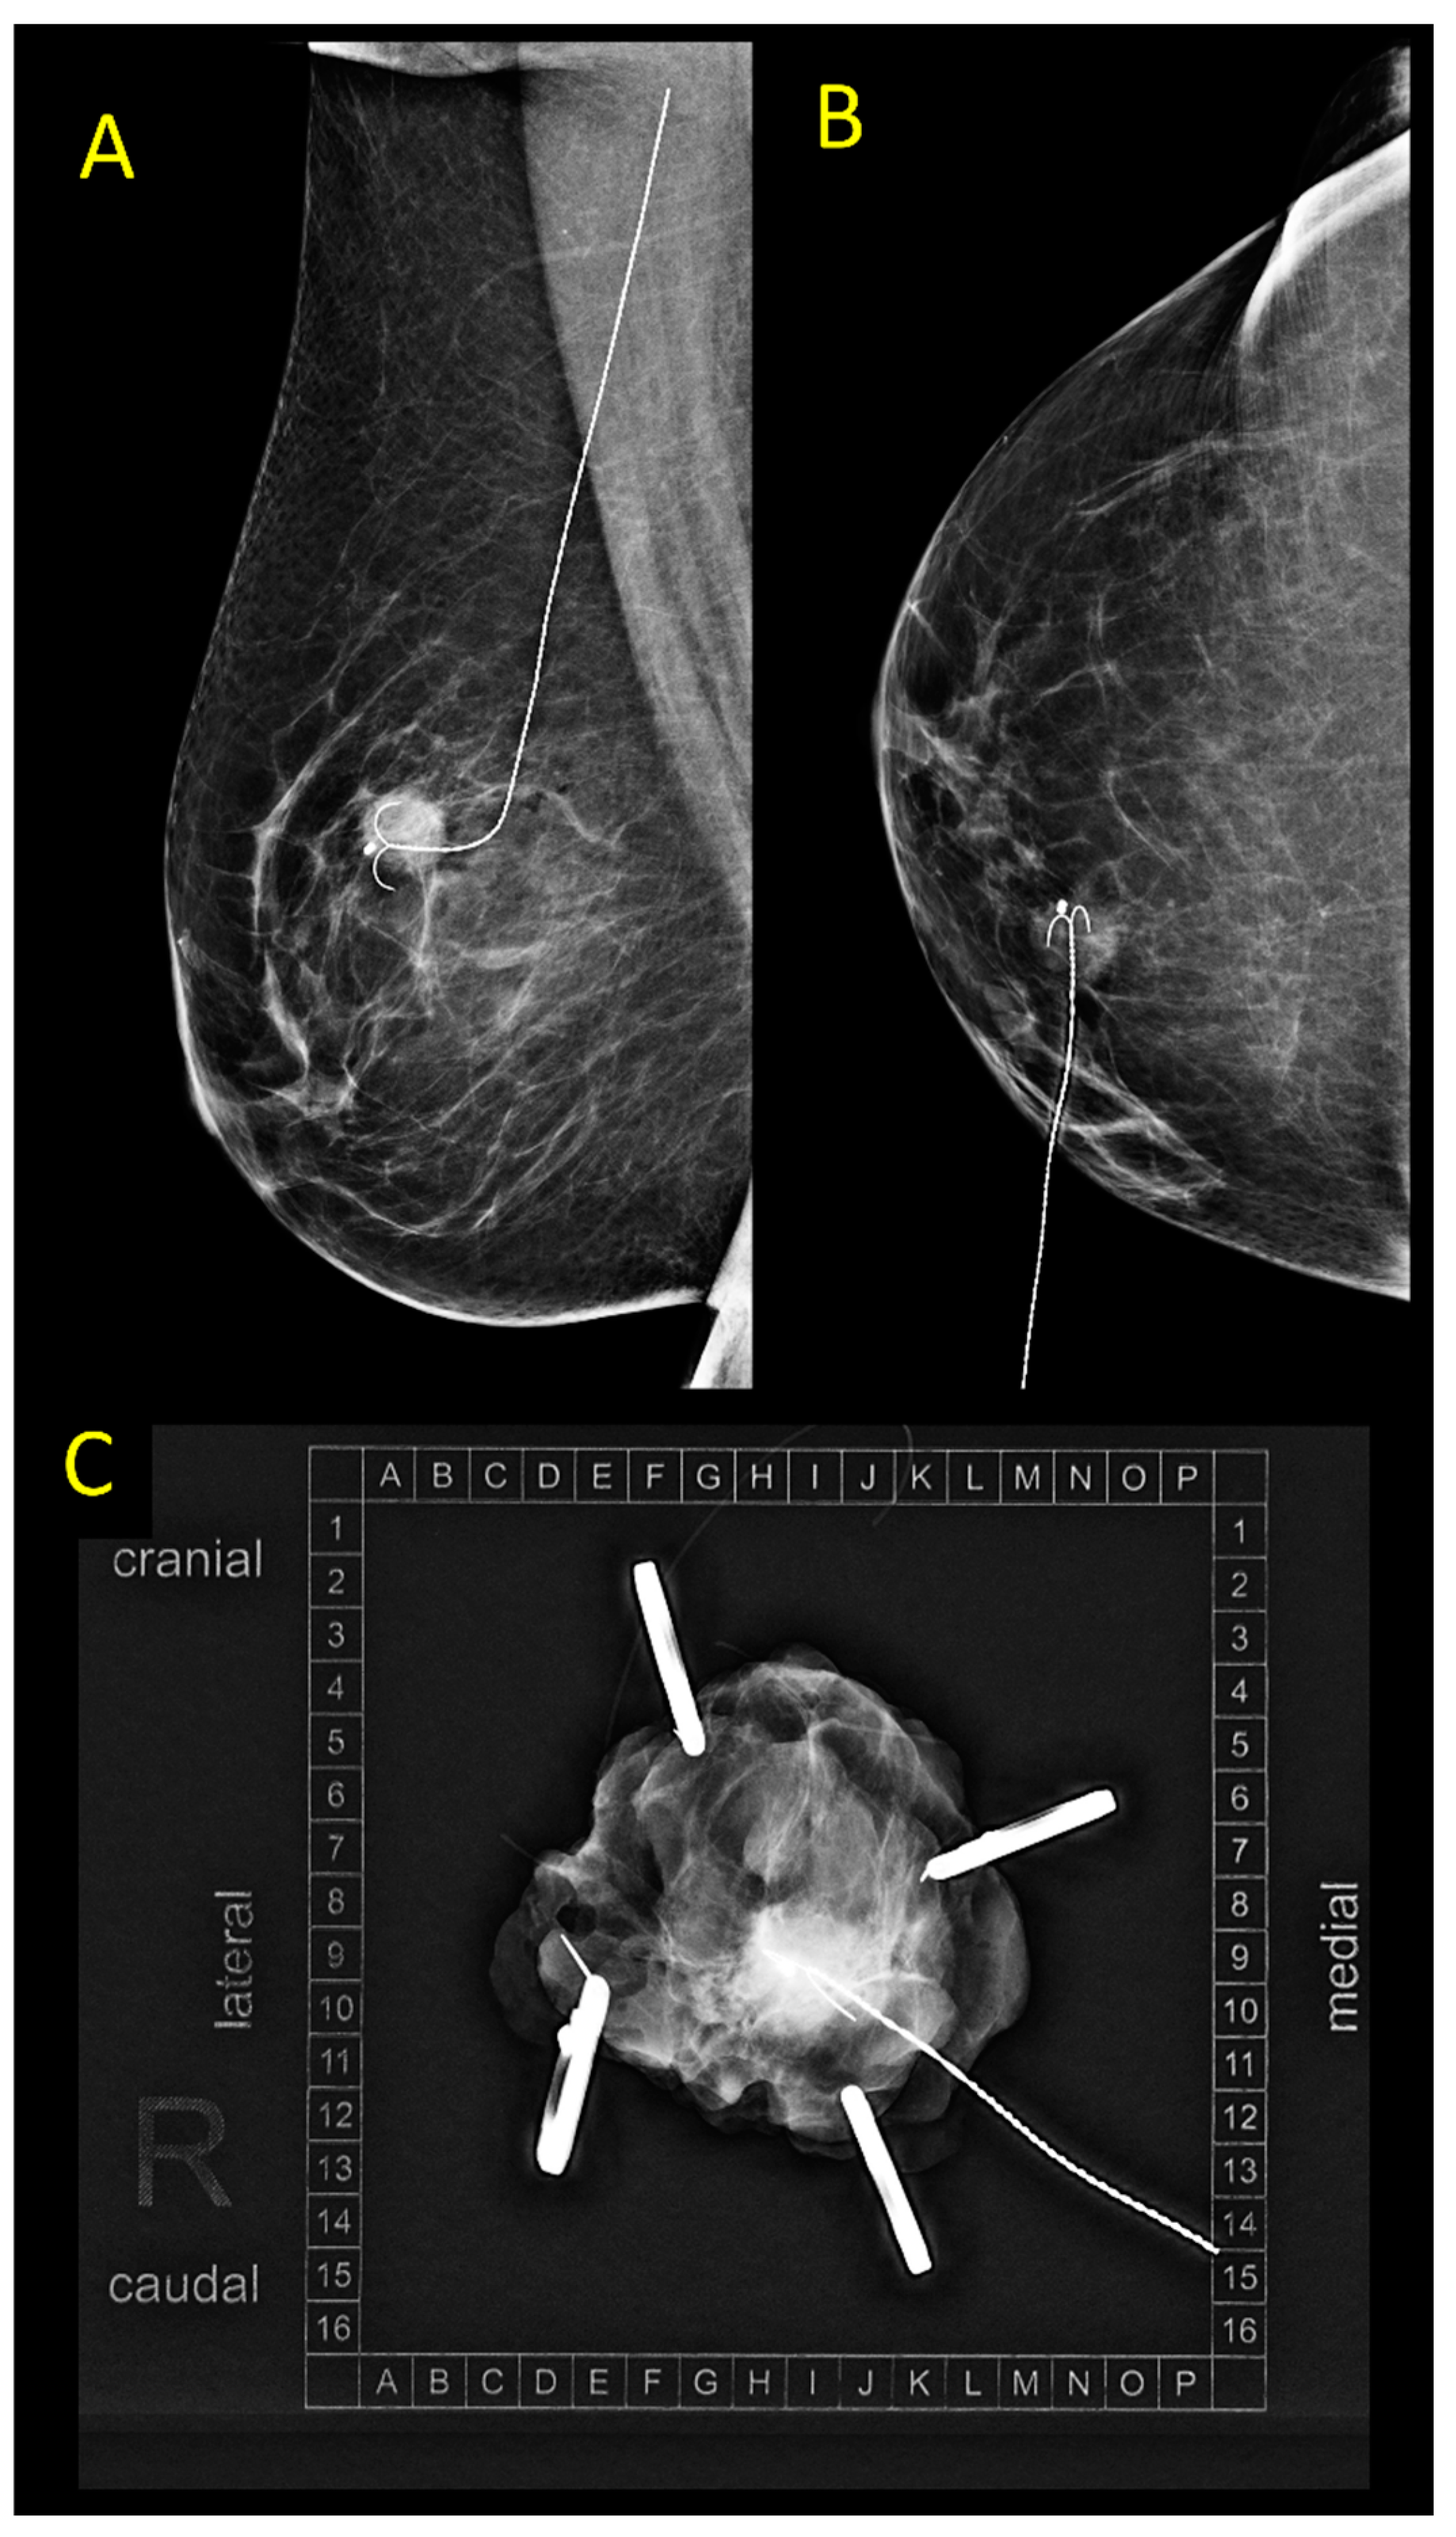

2.1. Wire-Guided Localization (WGL)

2.5. Radar Reflector Localization